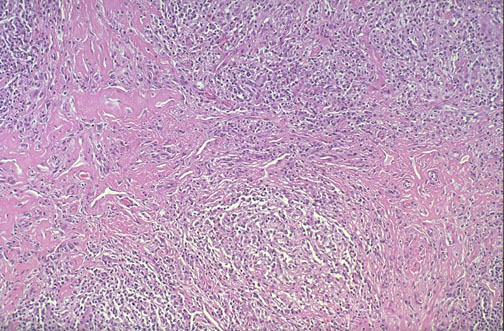

| At medium power, nodular sclerosing Hodgkin lymphoma has prominent bands of fibrosis. Staging of Hodgkin lymphoma is important to try and determine therapy and the prognosis. Staging is often done by radiographic means, with CT scans used to determine where lymphadenopathy is located, ultrasonography to determine size and lesions of liver and spleen, and chest radiograph. Histologic diagnosis is typically made from biopsy of an involved lymph node. A bone marrow biopsy is typically performed as well. Staging laparotomy is less commonly used nowadays because the radiographic procedures are excellent. |